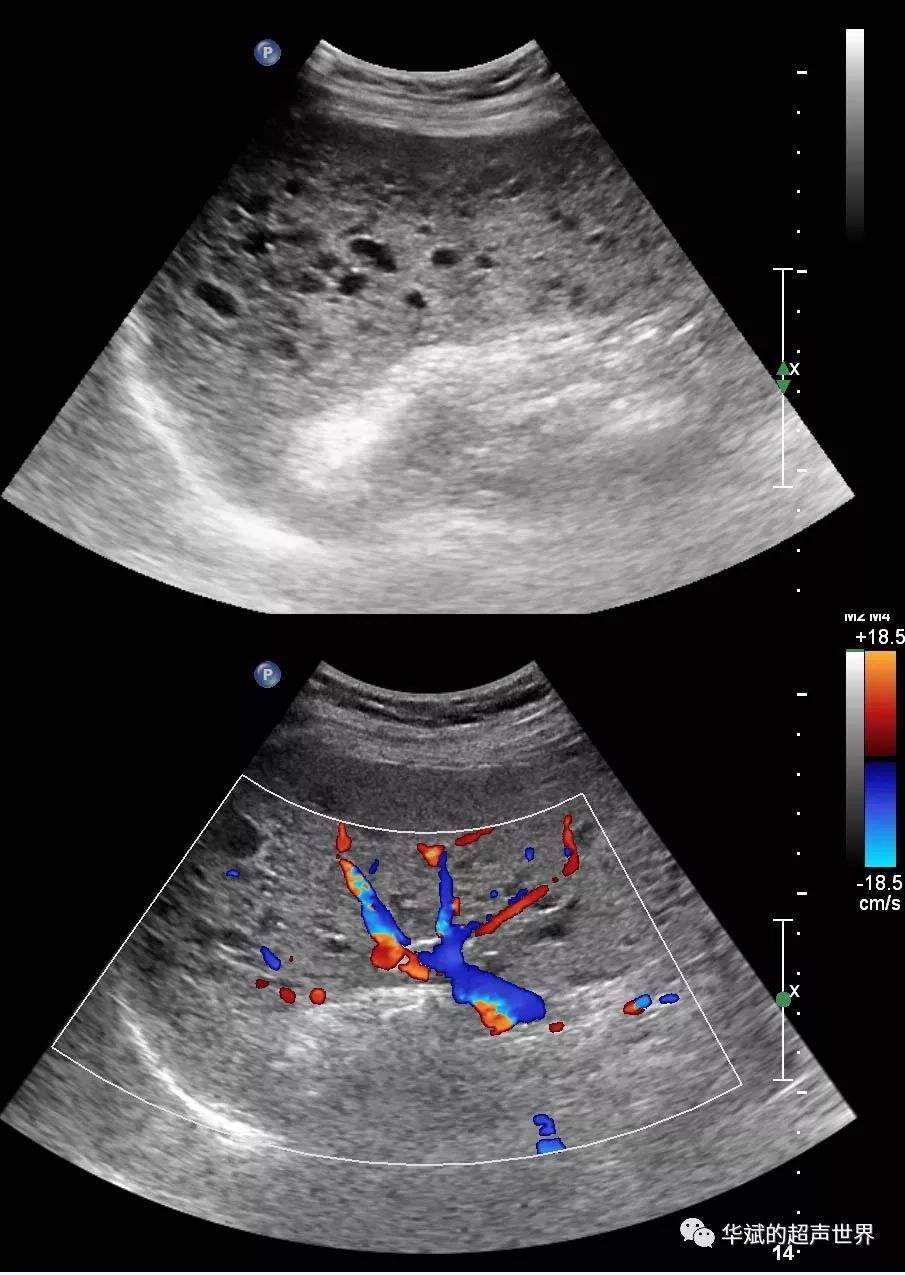

一、脾大的原因:

一、引起脾大原因有很多,比如说感染性脾大,各种急慢性感染和伤寒、副伤寒、黑热病、血吸虫病、痢疾、病毒性肝炎,败血症、晚期梅毒等,失血性脾肿大、班替氏综合征、肝硬化、慢性心力衰竭、至心源性肝硬化、慢性缩窄性心包炎,门静脉或脾静脉血栓形成。

二、增生性脾大,见于某些血液病,如白血病、溶血性贫血、恶性淋巴瘤、脾脏恶性肿瘤较罕见,脾脏囊肿、散播性红斑狼疮、皮肌炎、结节性多动脉炎、高雪氏病,因脾脏大多较复杂,除少是人的生理外,都应在医生的指导下寻病因,并要定期复查,脾大的原因和治疗的方法是互相相融的,知道了引起脾大的原因,那么就需要及时找到针对性的治疗方法,患者可以采用食疗来缓解或控制病情,也可以通过手术切除方法来治疗,这样可以起到立竿见影的效果。

二、脾大可以自己恢复吗?

脾大是否可以自行的恢复。最主要根据引起脾大原因决定。如果是感染,出现的感染性脾脏肿大,脾大多数为轻度,会伴有压痛感。在感染控制以后,短期内就可以恢复。如果因为肝硬化,而引起的脾脏肿大,脾脏自行恢复的可能性比较小。如果是血循环所导致的脾脏肿大,需要治疗原发病后,脾脏肿大才能有所恢复。

三、脾大的治疗

需要针对脾肿大的原因积极治疗,生理性脾肿大,常在体检时被发现,属于健康人群,没有不适症状,不需要治疗。血液系统疾病引起的脾肿大,需要针对血液疾病的病因进行治疗。门静脉高压导致的脾肿大,需要积极持续药物治疗,积极治疗原发病,降低门静脉压力,还可以介入手术治疗。感染性疾病引起的脾肿大,需要积极控制感染。